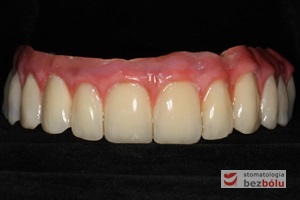

Gotowa praca protetyczna - korony cerkonowo-ceramiczne na modelu roboczym dostarczone z laboratorium protetycznego

Gotowa praca protetyczna – korony cerkonowo-ceramiczne na modelu roboczym dostarczone z laboratorium protetycznego

Ostateczny efekt estetyczny wieńczący proces terapeutyczny - odbudowa protetyczna obu łuków zębowych przy zastosowaniu implantów Friadent Ankylos

Ostateczny efekt estetyczny wieńczący proces terapeutyczny – odbudowa protetyczna obu łuków zębowych przy zastosowaniu implantów Friadent Ankylos